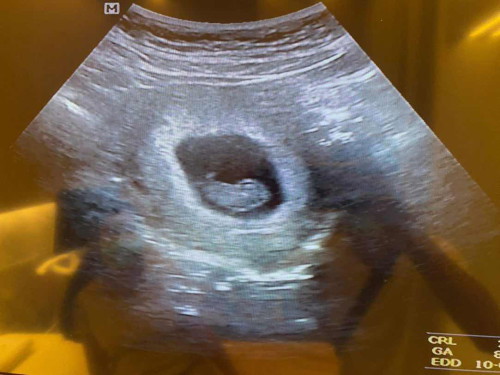

8วีคแล้ว ควรทานอาหารแบบไหนคะ หรือบำรุงด้วยการทานนมแบบไหนดีคะ

ยังไม่ได้ฝากครรภ์เลยค่ะ #ขอคำแนะนำหน่อยค่ะ #คุณแม่ๆช่วยแนะนำหน่อยค่ะ